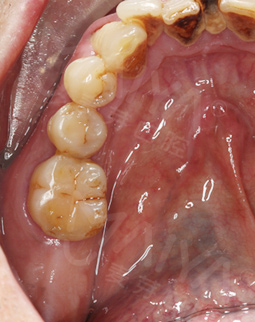

今天很早来到了院内,恰逢这里启动疑难缺牙修复工程,全城征集疑难缺牙案例,我果断报了名。由于缺牙时间长,牙槽骨吸收严重,骨量不足,给种牙带来了一定的难度,符合征集条件,于是很荣幸成为了"疑难种牙直播间"的案例主角。

经过医护人员的严密术前检查和准备工作后,顺利进入了三通道无菌手术室,接受种植博士专家团此前为其量齿定制的全数字化精确种植牙手术,一颗牙种出来真的只需要5分钟,我还没有任何感觉,医生说已经种好了,不得不感叹科技技术发展快、医生技术高超,而且第一次种牙就赶上了“工程”行动,非常幸运,对我们普通百姓来说"工程"援助非常实在,希望"工程"启动能帮助更多的人,毕竟缺牙人很多,祝愿大家都能像我一样在麦芽口腔种好牙,享口福。"